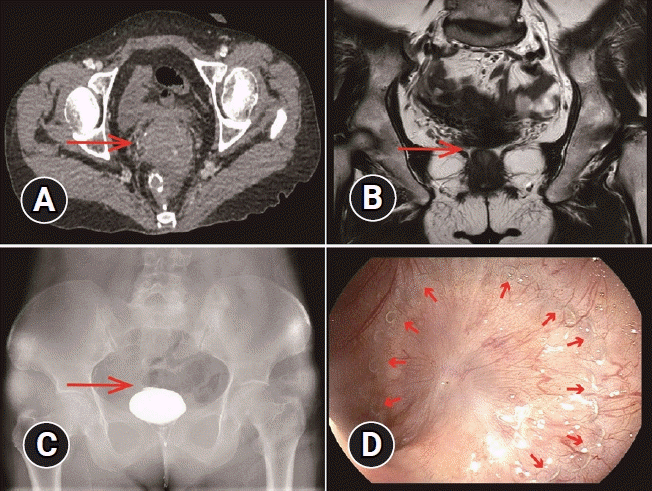

Three months later, the patient underwent ileostomy reversal. Prior to the reversal, a comprehensive diagnostic evaluation was performed. Abdominal computed tomography, magnetic resonance imaging, barium enema, and endoscopy revealed complete membranous atresia at the ileorectal anastomosis site (Fig. 1). Owing to the significant trauma and risks associated with surgery, and with the consent of the patient and her family, we opted for endoscopic resection to address the issue. The procedure was monitored using two endoscopes, with surgery considered as an alternative approach.

Fig. 1.

Imaging findings. (A, B) Abdominal computed tomography and magnetic resonance imaging images depicting the narrowing of the intestinal lumen at the anastomotic site (arrow). (C) Barium enema revealing barium in the middle and lower parts of the rectum with no contrast agent entering the ileum (arrow). (D) Endoscopy revealing complete closure of the anastomotic site surrounded by anastomotic nails (arrows).